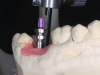

While guide fabrication has advanced since the simple guide described above and there are other methods for making guides, CAD/CAM is the most efficient, accurate, and cost-effective way to create a precision surgical guide.16 Depending on the system, the CAD/CAM guides may be milled or printed out of a rigid plastic. Sirona Dental Inc.’s CEREC® system (www.cereconline.com) uniquely allows for small guides to be produced in the office out of a thermoplastic material and a small milled insert (Figure 11). While this solution is only appropriate for some cases, it does allow guides to be made in minutes for about $30, enabling this procedure to be done for routine single implants in a cost- and time-effective manner. Laboratory-made guides can vary in cost from about $200 to $450 depending on the manufacturer and number of implants. With the integration of CAD/CAM and CBCT, guides have gone from an expensive, cumbersome, inaccurate adjunct to a routine part of the implant procedure (Figure 12).

Fig. 16 through Fig. 18 The CEREC Guide was made in the office from a thermoplastic material (yellow). Initially, a radiographic insert (white) was embedded and placed in the mouth during the CBCT scan. After the implant was planned, a drill guide (clear) was milled and inserted into thermoplastic housing. The guide was ready for surgery.